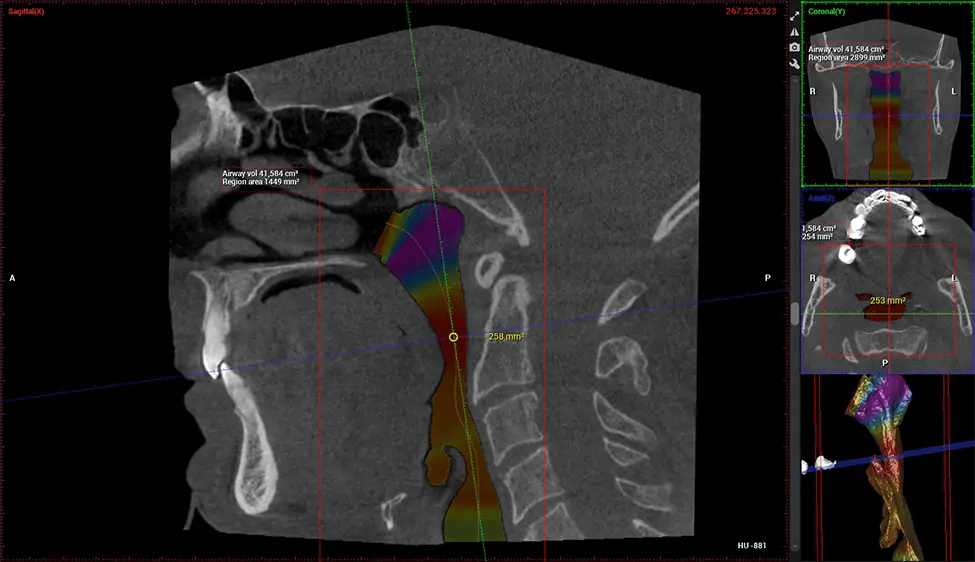

Cone Beam Computed Tomography (CBCT) is an advanced imaging technique used in dentistry and maxillofacial surgery to obtain detailed 3D images of the oral and maxillofacial structures. At Dr G Dental Studio, our CBCT scanners utilize a cone-shaped X-ray beam and a specialized detector to capture images from different angles. A computer then combines these images to create a 3D representation of the patient’s oral anatomy.

This 3D scan, called cone beam computed tomography, gives your dentist a more complete image of your oral anatomy and disease processes than a traditional X-ray. Unlike conventional X-rays, which capture a 2D image of your mouth from various angles, a 3D scan takes multiple digital X-rays for one image. It provides a complete view of your jaw, teeth, nerves, and soft tissues. This enhanced view allows dentists to detect minor issues not visible in traditional 2D scans, such as impacted wisdom teeth or bone fractures in the sinus cavity.

After the scanning process, the captured X-ray images are processed by the CBCT software, which applies algorithms to reconstruct a detailed 3D image of the scanned area. The software compiles these individual X-ray images and creates a digital 3D representation of the patient’s anatomy. The reconstructed 3D CBCT image can be viewed and analyzed by the dentist or radiologist. This image can be manipulated, rotated, and zoomed in or out to examine specific structures and evaluate the patient’s condition.

ENT Physician Diagnosing obstructive sleep apnea (OSA) and evaluating sinus and nasal cavity anatomy. Visualizes the entire pharyngeal airway to measure volume, pinpoint constrictions, and plan corrective surgery if needed.

Screening and treating patients at risk for OSA.

Provides detailed 3D imaging for airway analysis, helping to create and adjust oral appliances and facilitate effective referrals to medical doctors.